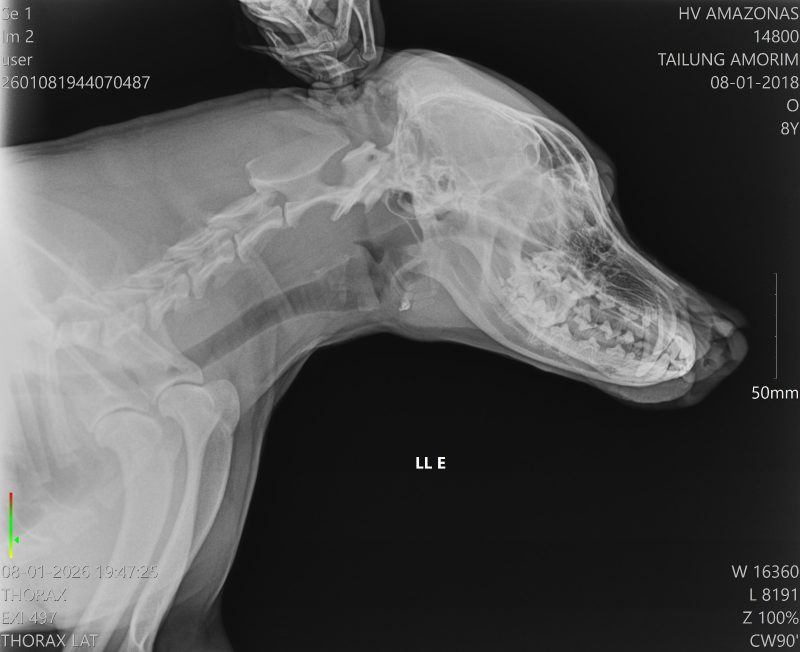

Um cachorro foi socorrido na noite de quinta-feira (08/01), na comunidade Nossa Senhora do Livramento, no igarapé do Tarumã-Mirim, à margem esquerda do Baixo Rio Negro, zona Oeste de Manaus, após ser golpeado no focinho com um terçado.

O animal foi levado pelo tutor ao Hospital Público Veterinário do Amazonas (HPVet-AM), onde recebeu atendimento especializado.

Segundo a equipe médica, o cachorro apresentava lesão profunda na região do focinho, mas chegou consciente à unidade e respondeu bem aos procedimentos. Ele passou por avaliação clínica e cirurgia, que foi considerada bem-sucedida.

Após o atendimento, o animal recebeu alta e já está em casa, onde permanece em observação sob os cuidados do tutor, com acompanhamento da equipe multidisciplinar do HPVet-AM para garantir a recuperação completa.